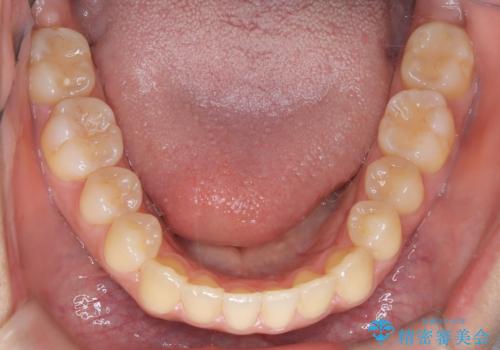

- 患者様は左上の八重歯を気にされて来院されました。八重歯による歯列の乱れだけでなく、翼状捻転(歯がねじれるように生えている状態)も見られました。目立たない矯正を希望されていたため、**インビザライン(マウスピース矯正)**を選択し、左上の小臼歯を抜歯してスペースを作りながら歯を並べる治療計画を立てました。しかし、治療の途中で翼状捻転の改善が十分に進まなかったため、患者様の希望も踏まえ、上顎のみワイヤー矯正に変更することとなりました。

治療開始時はインビザラインを使用し、全体の歯並びを整えながら抜歯スペースを活用して歯を後方へ移動させました。しかし、左上の八重歯のねじれが強く、マウスピースのみでは十分にコントロールできないことが判明。そこで、より細かく歯を動かすために上顎のみワイヤー矯正へ切り替えました。ワイヤー矯正によって翼状捻転も改善し、最終的にバランスの取れた歯並びと噛み合わせを実現。患者様からは「長い治療だったけれど、しっかり整って満足」と嬉しいお言葉をいただきました。